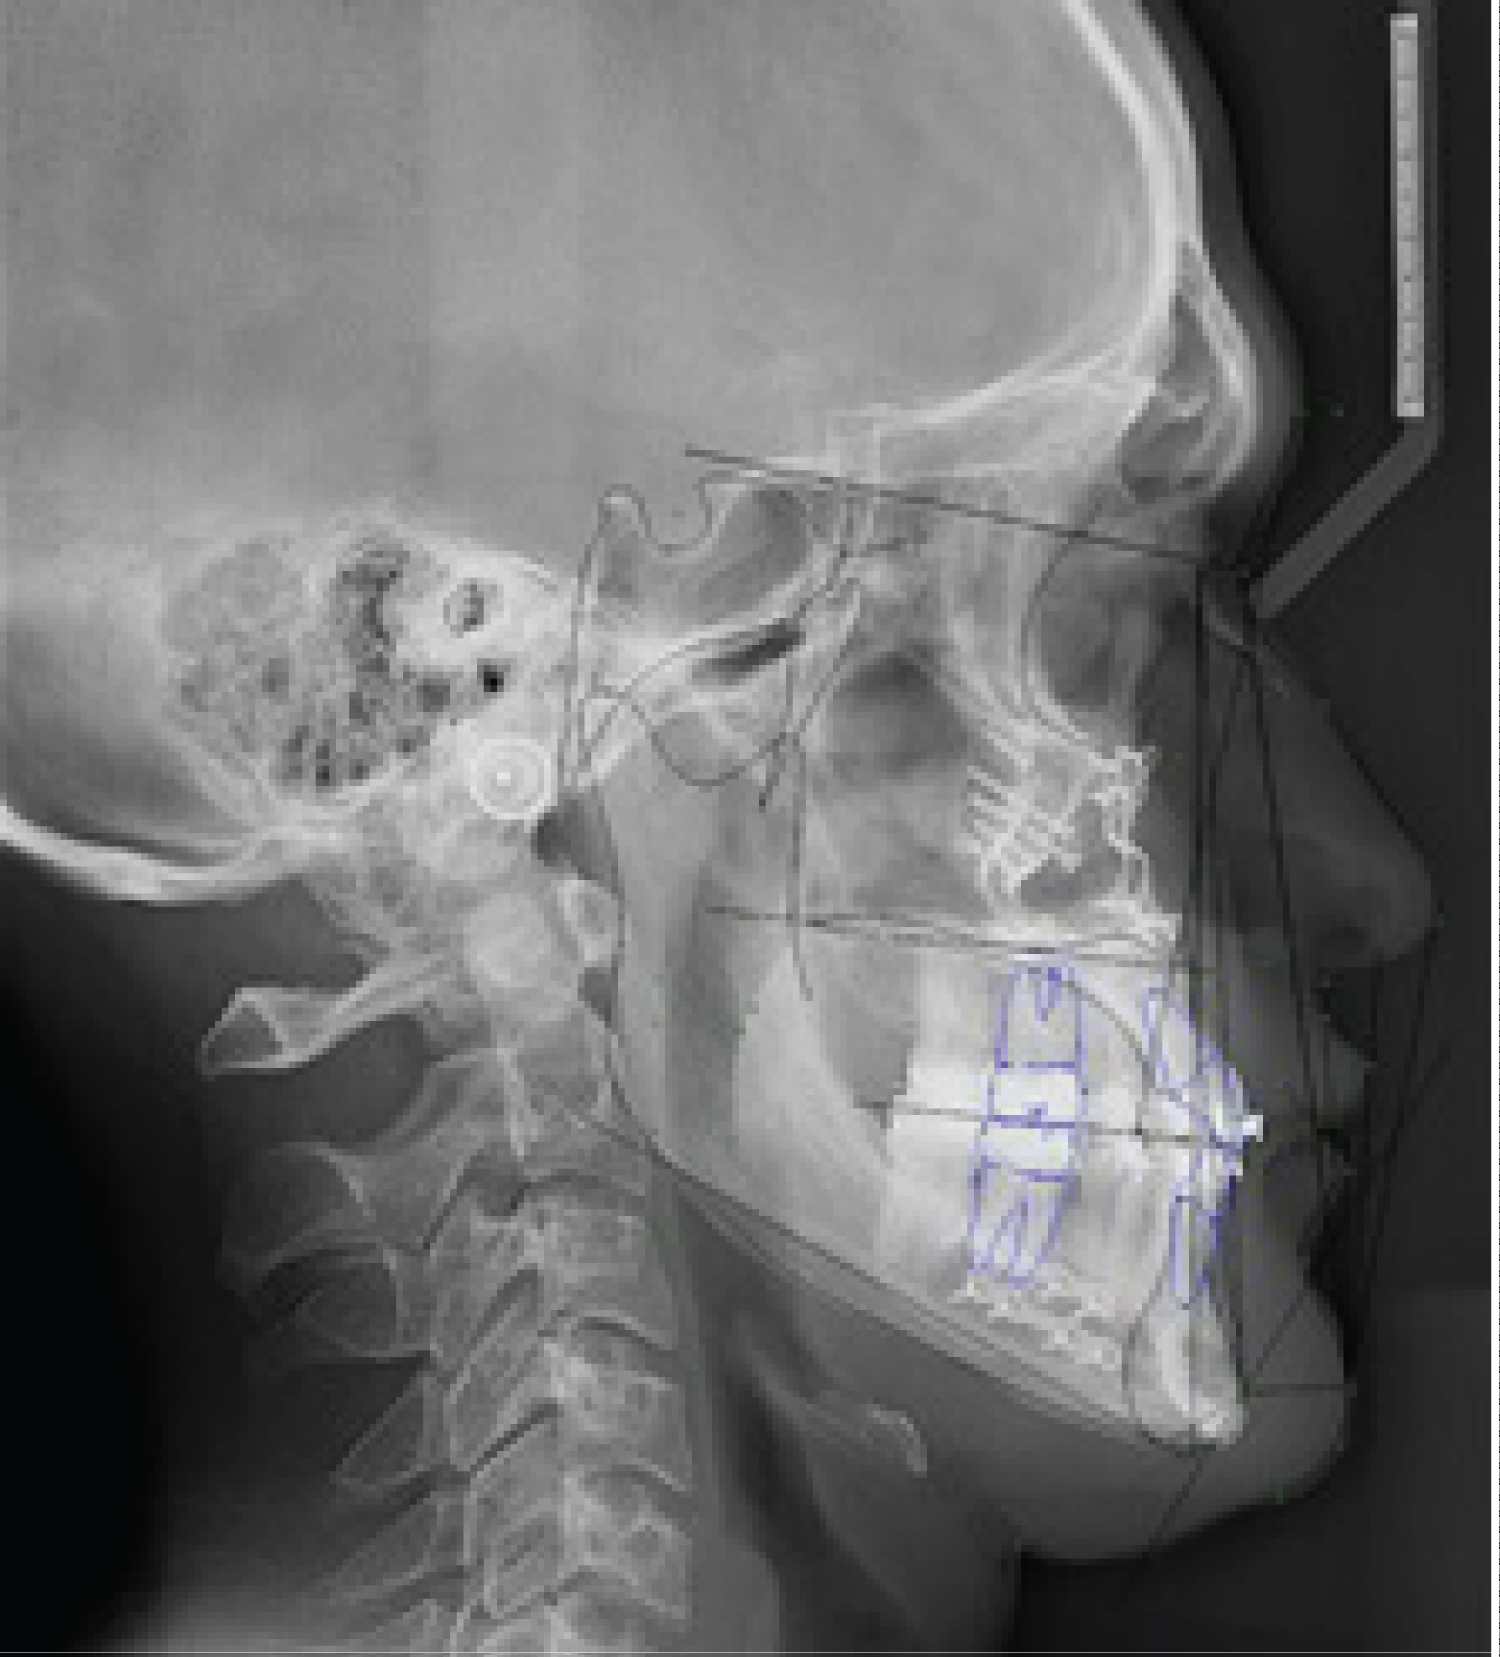

In the case of the patients presented, the changes are exposed to the naked eye and aesthetics, but they are also expressed according to facial analyzes, for example, in the patient 1, following the reference of the Burstone and Legan Analysis [12], the distance to level of hard tissues from the Nasion point to the Pogonion, which indicates the prominence of chin in relation to profile went from being 35.3 mm to 21.5 mm and in patient 2 a, even a decrease in mandibular length measured from the Gonion to the Pogonion from 81.5 to 76.8 mm (Figure 6, Figure 7, Figure 8, Figure 9 and Figure 10).

Figure 10: Patient 2: Control cephalometry 6 months after surgery. View Figure 10

In the case of patient 2, following the Burstone-Legan analysis [12], the distance between Point B and the Pogonion [10], which represents the degree of anterior projection of the chin, decreased from 12.6 to 8 mm, as in patient 1 who decreased this distance from 14.6 to 8.3 mm, which indicates a decrease or elimination of the Macrogenie. It is worth mentioning that in these two cases the Genioplasty is performed as a complementary procedure in the context of an Orthognathic Surgery, which there are values that have to be analyzed in relation to the joint procedure. Genioplasty as a technique is described as an extremely versatile, leading to predictable and long-lasting results improving appearance in aesthetics and functionality by reorienting both bone and muscle, and if well, it is defined as a low-risk procedure, the alteration at the neurosensory level is present due to the soft tissues that surround the mental nerves and is so it should always be taken into account to reduce its incidence and in case of introduce yourself, know how to handle it.